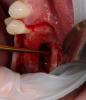

CSS Опубликовано 26 декабря, 2012 Автор Поделиться Опубликовано 26 декабря, 2012 1-й сектор сделан точно также, только проведена дополнительно НКР с тем же Алло!!!! Ссылка на комментарий

CSS Опубликовано 26 декабря, 2012 Автор Поделиться Опубликовано 26 декабря, 2012 спасибо, хорошие фотки. А почему эксперимент?Такое впечатление по ОПТГ после синусов, что в 1 сегменте графт пополз скврзь мембрану, как бы нет уровня имхоСпасибо за кейс.Эксперимент с Алло, это немецкий материал, смесь кортикальной и губчатой кости. Использовал впервые. Относительно проползания графта, там очень сложная анатомия была, за 3 мес до этого было удаление с перфами. Слизистая утолщена, и отслоена целой. Рентген - это доп метод!!! ;-))) Под слизистой Prp и Алло мембрана из фасции!!! Ссылка на комментарий

CSS Опубликовано 26 декабря, 2012 Автор Поделиться Опубликовано 26 декабря, 2012 чем отслаивали окно в синус от мембраны?какой алло материал использовали? И пропилы и отслойка, пьезо, далее кюретами. Тут Даск. Про Алло, материал Остеографт, пока не зарегиный в РФ, смесь кортикалки и губки!!! Производят немцы. Ассортимент масштабный, есть и комбинирированные гиалуронкой и деминерализированные, но я хочу сам разобраться, что лучше и интереснее для меня. Цена реально смешная, по сравнению с синтетиками и ксенографтами. Ждемс результатов. Через 4 мес контр КТ и решим, что там выросло, а то мож на эндоскопическую санацию синуса прийдется пацика посылать!!!! ;-)))))) Ссылка на комментарий

CSS Опубликовано 26 декабря, 2012 Автор Поделиться Опубликовано 26 декабря, 2012 по вашему кейсы - импланты углубил бытакое впечатление что в области 25 не хватает графтаокно сделал бы меньше (есть же даск). ваш кусок может секвестрироватьсянужно стандартизировать фотопротокол а так все норм. спасибо за кейсработаю алло почти 2 годавсе нравится и ничего там не нагнаивается - для доктора шу Спасибо за комментарий, но окно намеренно делалось таким, ввиду сложной анатомии в зоне 26 и 27. У меня есть Даск, и очень прикольный набор, но лично по мне не всегда применим, ввиду длинной ножки бора, об этом мы еще пополимеризуем на конгрессе в Краснодаре!!!!!! ;-)))) В зоне 25 все ок!!! Просто этот граф не всегда контрастен. А деминерализованный алло вообще не виден после операции, и бывало ощущение, что винты в воздухе, но контрольное кт, развеяло сомнения!!! ;-)))Относительно углубления, если б это был Дентиум, то углубил бы на 0,5, но тут Горизонт, о своих наблюдениях уже писал выше!!!Насчет фотопротокола, ну не всем так везет, иметь штатных профессиональных фотографов, так что не обессутьте!!! ;-))) А как у Вас с аллоблоками??? Каков протокол??? Вымачиваете??? Какую толщину ламината используете??? Ссылка на комментарий